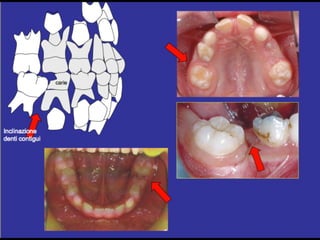

Dental anomalies in Cleft lip and palate patients

• The incidence of dental anomalies is

54%(15% normal population)

• Missing teeth

• Supernumerary

• Enamel hypoplasia

• Morphology anomalies

• Impacted teeth (1

• Missing upper lateral incisor (30-50%)

⬥In deciduous dentition some teeth could be smaller in

the cleft side

⬥Males- laterale incisor and second molar

⬥Females - central and lateral incisors

!

⬥In permanent dentition always lateral incisor

congenitally missing